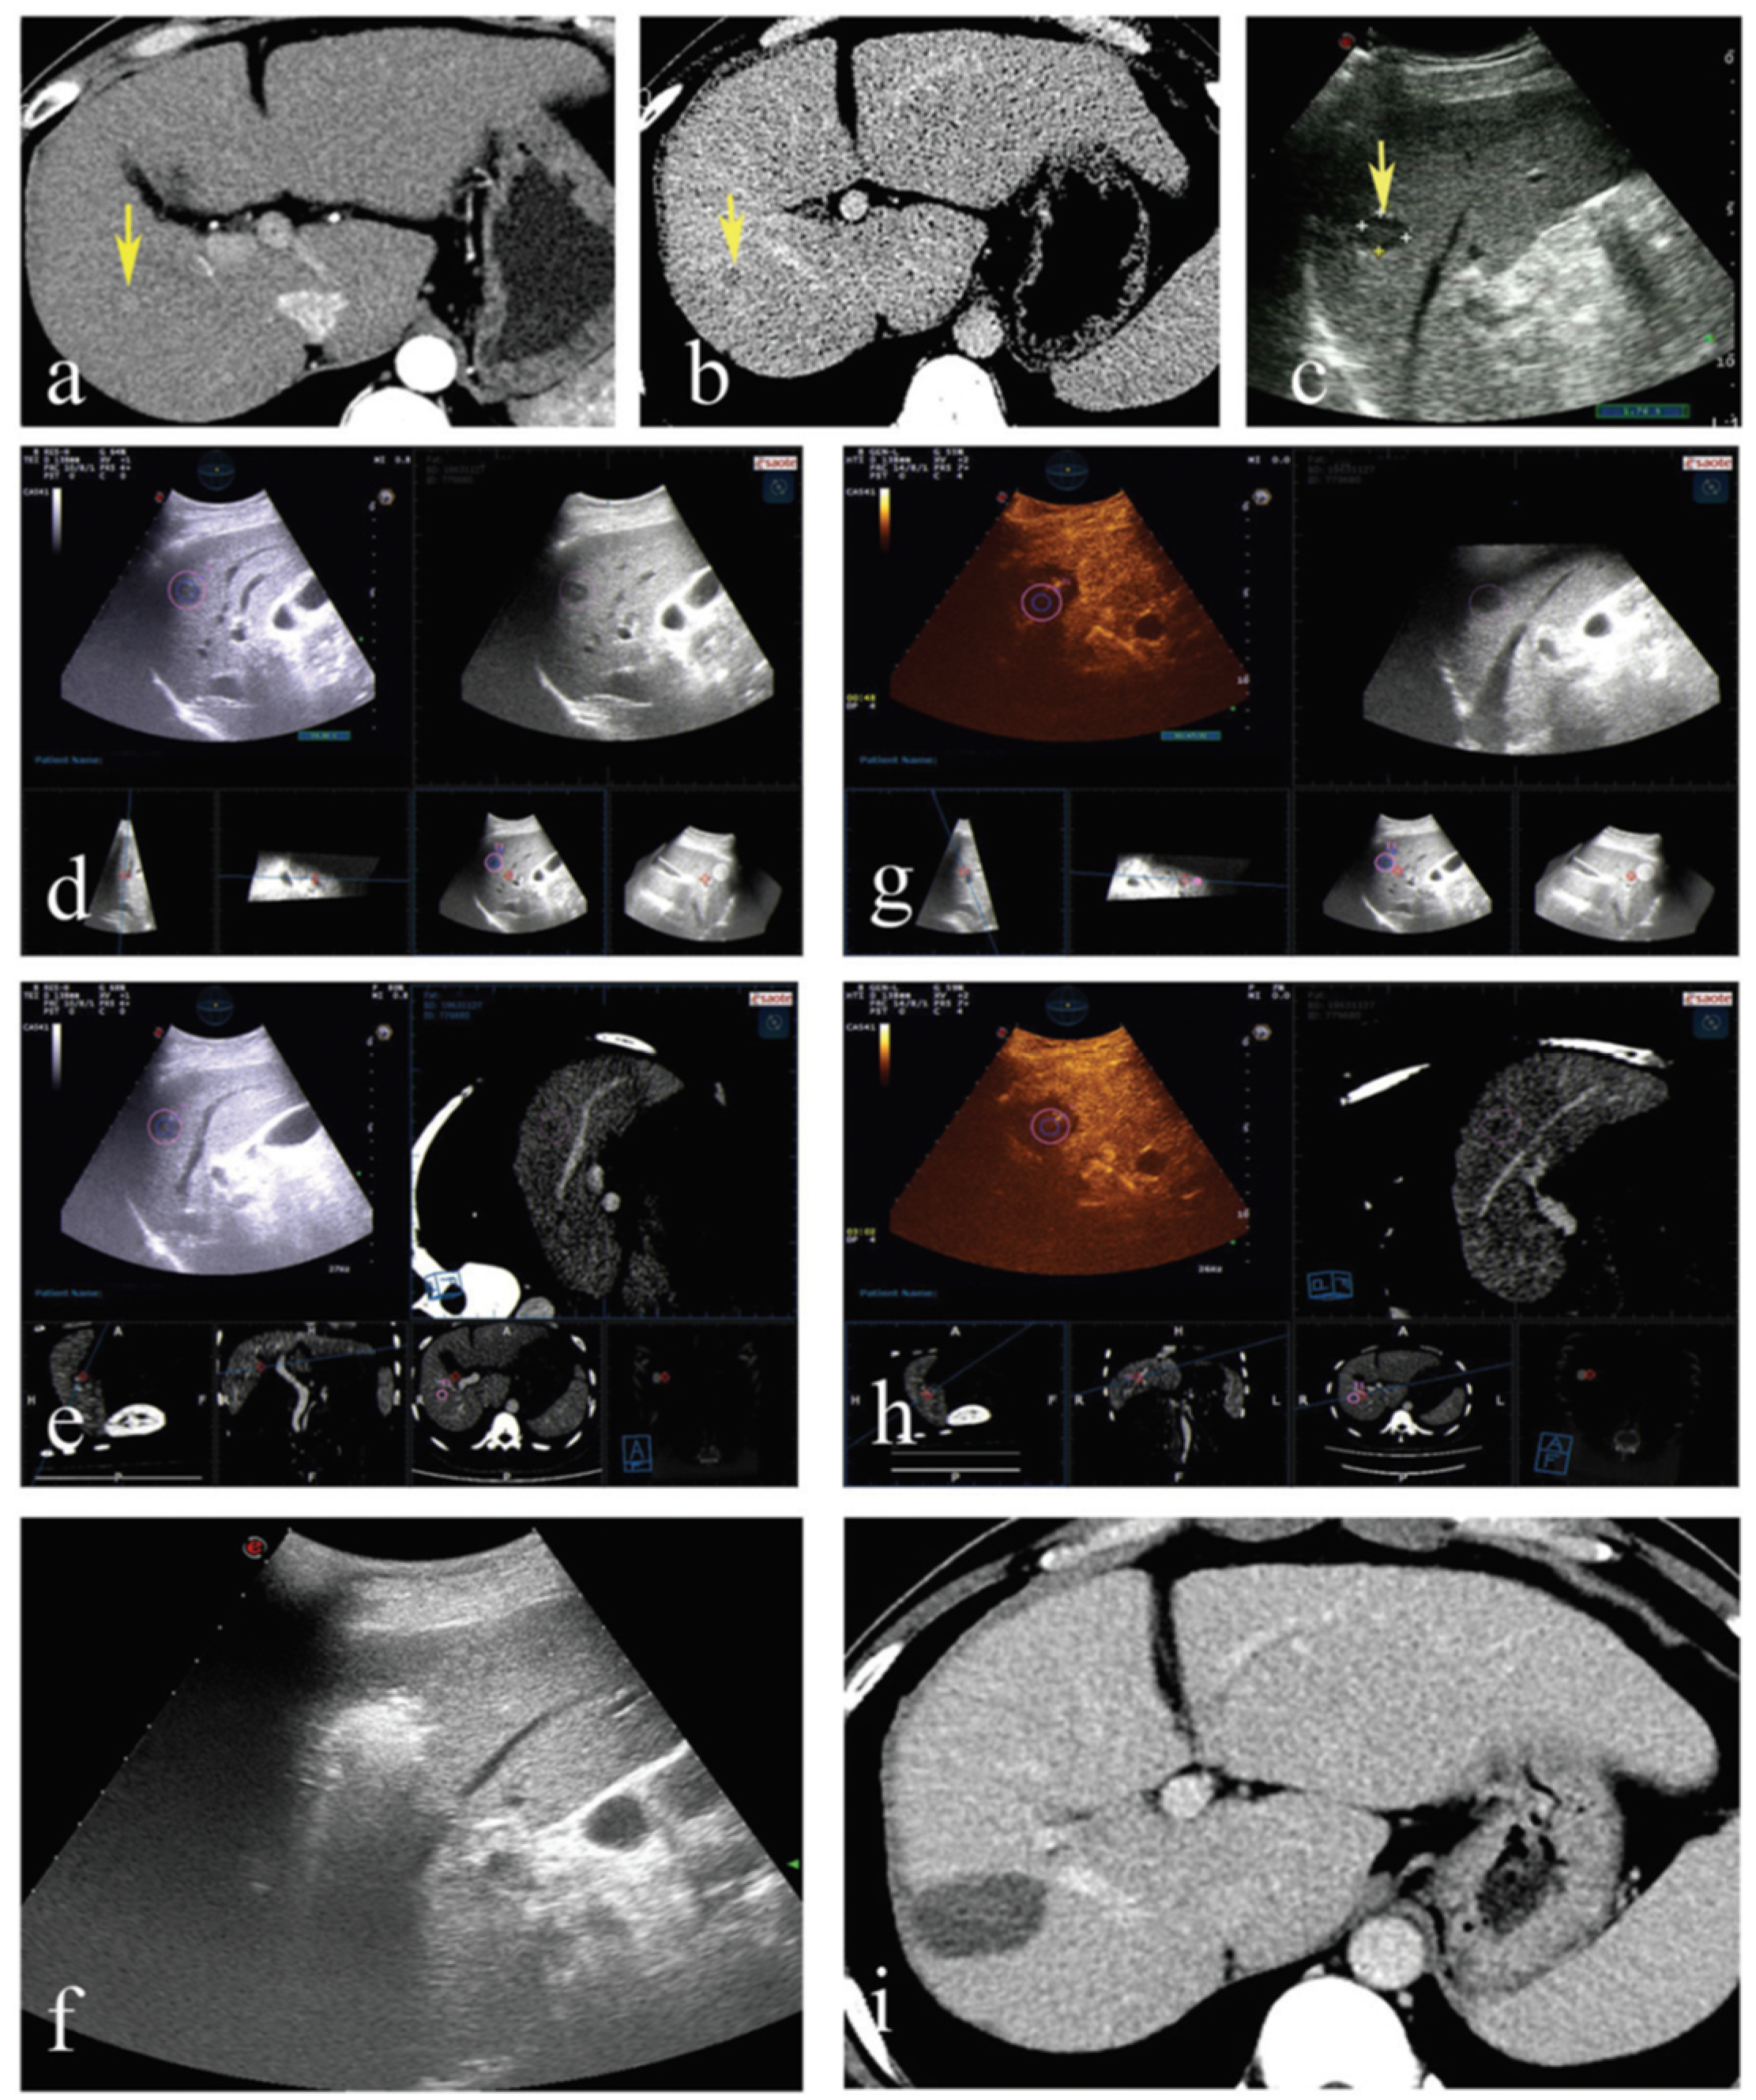

5.1. Ultrasonography/MRI, Ultrasonography/CT and Ultrasonography /PET-CT

5.1.1. Utility of CEUS/MRI in Diagnosis and Treatment of Small Liver Cancer

5.1.2. Utility of CEUS/MRI in Radiofrequency Ablation of Liver Cancer

5.1.3. Utility of CEUS/PET-CT in Transarterial Chemoembolization Treatment of Liver Cancer

- Xu, E.; Long, Y.; Li, K.; Zeng, Q.; Tan, L.; Luo, L.; Huang, Q.; Zheng, R. Comparison of CT/MRI-CEUS and US-CEUS fusion imaging techniques in the assessment of the thermal ablation of liver tumors. Int. J. Hyperth. 2018, 35, 159–167. [Google Scholar] [CrossRef]

- Jung, E.; Schreyer, A.; Schacherer, D.; Menzel, C.; Farkas, S.; Loss, M.; Feuerbach, S.; Zorger, N.; Fellner, C. New real-time image fusion technique for characterization of tumor vascularisation and tumor perfusion of liver tumors with contrast-enhanced ultrasound, spiral CT or MRI: First results. Clin. Hemorheol. Microcirc. 2009, 43, 57–69. [Google Scholar] [CrossRef]

- Lee, M.W.; Kim, Y.J.; Park, H.S.; Yu, N.C.; Jung, S.I.; Ko, S.Y.; Jeon, H.J. Targeted sonography for small hepatocellular carcinoma discovered by CT or MRI: Factors affecting sonographic detection. Am. J. Roentgenol. 2010, 194, W396–W400. [Google Scholar] [CrossRef]